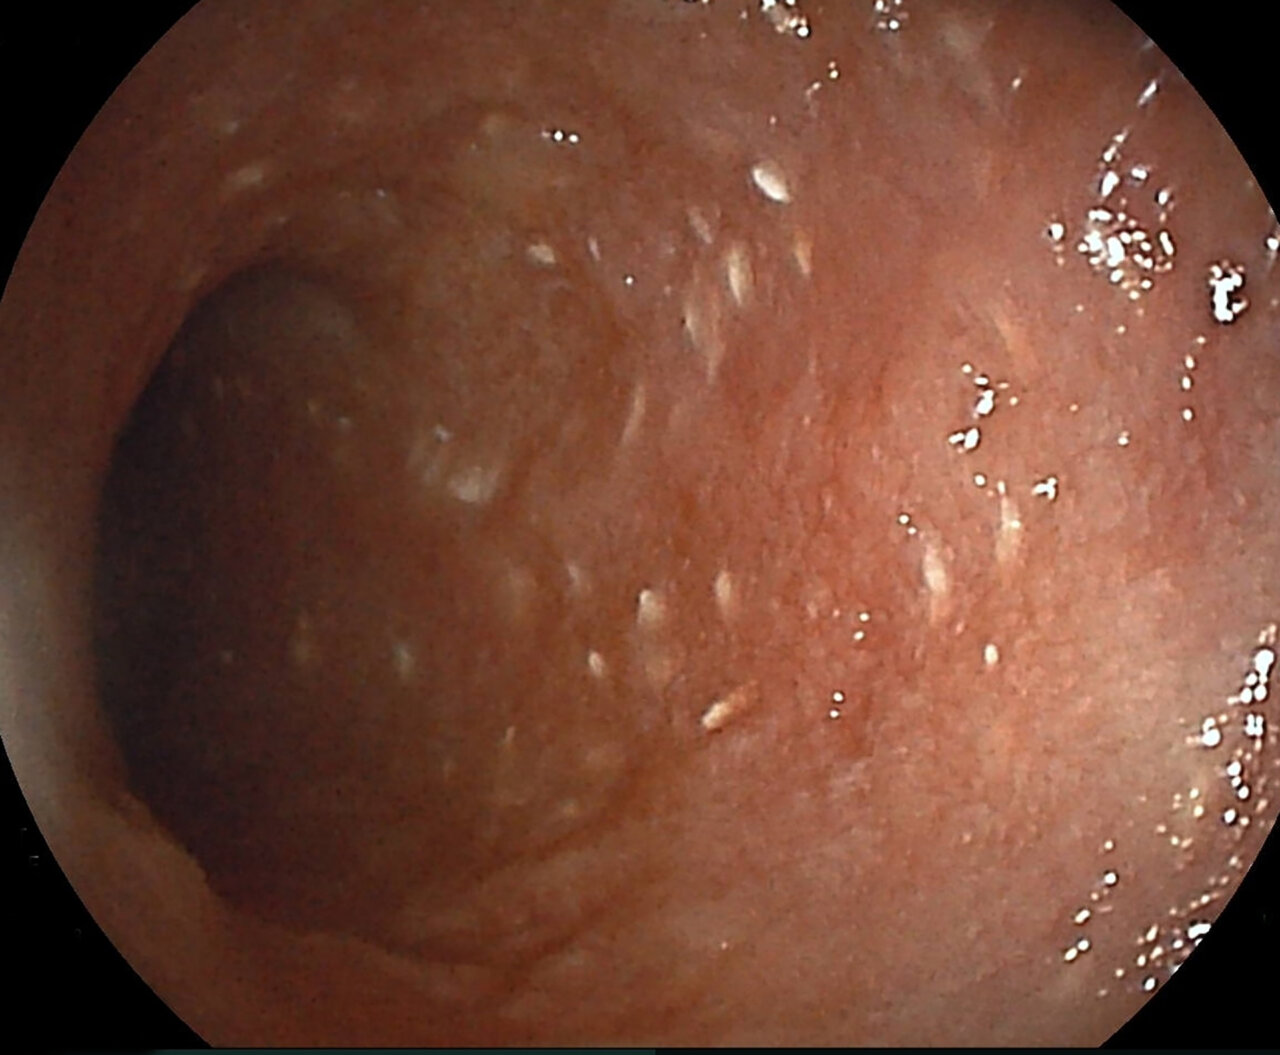

La biopsia y la histopatología de la pared intestinal son necesarias para un diagnóstico definitivo. Se ha puesto en duda en diversas ocasiones la validez de la biopsia endoscópica para la detección de linfangiectasia intestinal, pero un estudio más reciente mostró resultados similares a los que previamente se habían descrito en biopsias de espesor completo23. Teniendo en cuenta esto, en la mayoría de los casos la biopsia endoscópica será la primera opción (salvo presencia de lesiones focales), ya que se trata de animales que presentan alteraciones que podrían complicar la cirugía y posterior cicatrización, como el riesgo de trombosis, la hipoalbuminemia o el déficit de vitamina D. Además, la apariencia macroscópica también nos aporta información y puede guiar la toma de muestras (imagen 3).

Imagen 3. A y B) Imagen endoscópica de un paciente con linfangiectasia. Los puntos blancos que se aprecian en la mucosa duodenal se corresponden con conductos linfáticos dilatados con acúmulo de linfa en su interior. La biopsia confirmó la presencia de linfangiectasia intestinal, probablemente asociada a enteritis linfoplasmocitaria.